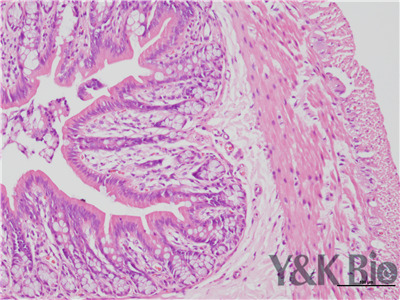

病理技术服务中HE染色法,学名苏木精-伊红染色,在法甘肃石蜡切片技术里是经常用的染色法之一。石蜡切片常用于观察正常细胞组织的形态结构,是病理学用以研究、观察及判断细胞组织形态变化的主要方法。苏木精染液是碱性的 ,主要使细胞核内的染色质与胞质内的核糖体着紫蓝色 ;伊红为酸性的染料 ,主要使细胞质和细胞外基质中的成分着红色。HE染色法是组织学、胚胎、病理学教学与科研中基本、使用广泛的技术方法。

HE染色中要注意细胞核的分化程度,注意苏木素和伊红的效价,及时更换染液,一般实验周期为15个工作日。